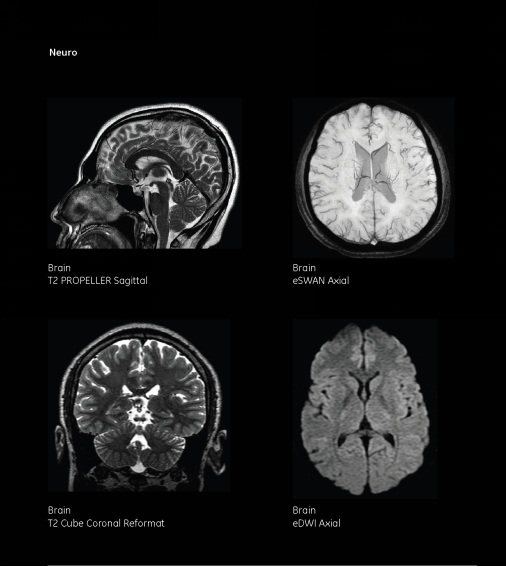

一、頭顱部

MRI在中樞神經系統(tǒng)成像效果最佳;①發(fā)現其他檢查方法易漏診的微小病變,如腔隙性腦梗塞、垂體微腺瘤、微小聽神經瘤、轉移瘤、腦干、小腦病變、靜脈竇病變、炎癥、脫髓鞘疾病及變性性疾病等。MRI彌散加權成像(DWI)可發(fā)現超早期、早期腦梗塞,利于早期治療,并常用于新、舊腦梗塞的鑒別診斷。

②磁敏感加權成像(SWI)對腦內小靜脈異常及微小出血可準確診斷;磁共振波譜(MRS)是可測得活體組織代謝物的化學成分和含量的檢查方法,有助于疑難病例的診斷和鑒別診斷。